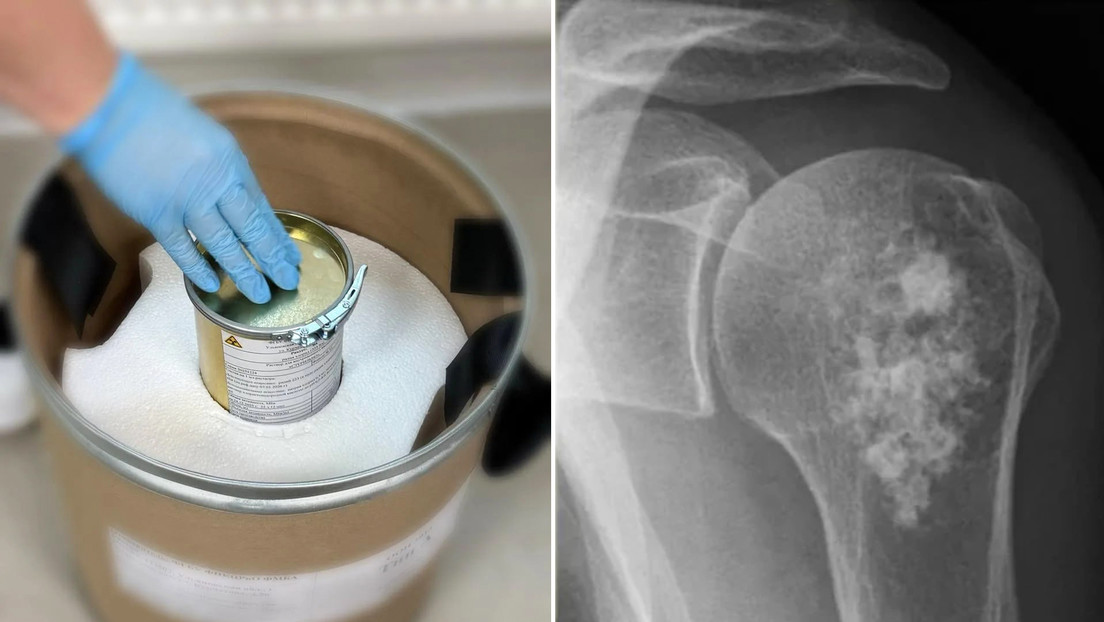

La introducción del fármaco es un hito para el desarrollo del sector de radiofármacos del país. Un...

Un equipo de profesionales del Hospital Universitario Gregorio Marañón ha logrado salvar la pierna de un niño...